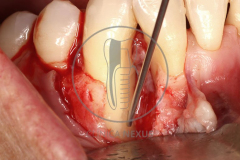

Tratamiento de defectos periodontales infraóseos en sector antero-inferior empleando gel de amelogeninas (Emdogain®) en combinación con un aloinjerto óseo (Biobank®). Paciente de 64 años, sin problemas médicos de relevancia, que presenta una periodontitis leve generalizada, pero asociada a presencia de defectos óseos verticales profundos a nivel de los espacios interdentales entre los caninos y los incisivos laterales inferiores. Tras la pertinente fase higiénica, se llevó a cabo una cirugía periodontal regenerativa, en la que, tras eliminar el cálculo subgingival (factor causal), se empleó una combinación de amelogeninas con un aloinjerto, para promover la regeneración tisular del periodonto perdido. Las imágenes clínicas y radiológicas, al año de seguimiento, reflejan un resultado terapéutico óptimo, con regeneración completa del tejido periodontal y mejora del pronóstico de los dientes involucrados.